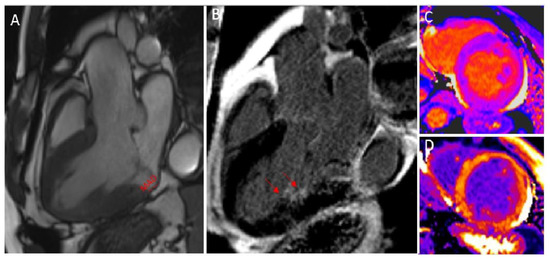

- Pavon, A.; Monney, P.; Schwitter, J. Mitral Valve Prolapse, Arrhythmias, and Sudden Cardiac Death: The Role of Multimodality Imaging to Detect High-Risk Features. Diagnostics 2021, 11, 683. [Google Scholar] [CrossRef] [PubMed]

- Marra, M.P.; Basso, C.; De Lazzari, M.; Rizzo, S.; Cipriani, A.; Giorgi, B.; Lacognata, C.; Rigato, I.; Migliore, F.; Pilichou, K.; et al. Morphofunctional Abnormalities of Mitral Annulus and Arrhythmic Mitral Valve Prolapse. Circ. Cardiovasc. Imaging 2016, 9, e005030. [Google Scholar] [CrossRef]

- Basso, C.; Marra, M.P.; Rizzo, S.; De Lazzari, M.; Giorgi, B.; Cipriani, A.; Frigo, A.C.; Rigato, I.; Migliore, F.; Pilichou, K.; et al. Arrhythmic Mitral Valve Prolapse and Sudden Cardiac Death. Circulation 2015, 132, 556–566. [Google Scholar] [CrossRef]

- Pavon, A.G.; Arangalage, D.; Pascale, P.; Hugelshofer, S.; Rutz, T.; Porretta, A.P.; Le Bloa, M.; Muller, O.; Pruvot, E.; Schwitter, J.; et al. Myocardial extracellular volume by T1 mapping: A new marker of arrhythmia in mitral valve prolapse. J. Cardiovasc. Magn. Reson. 2021, 23, 1–13. [Google Scholar] [CrossRef] [PubMed]

- Figliozzi, S.; Georgiopoulos, G.; Lopes, P.M.; Bauer, K.B.; Moura-Ferreira, S.; Tondi, L.; Mushtaq, S.; Censi, S.; Pavon, A.G.; Bassi, I.; et al. Myocardial Fibrosis at Cardiac MRI Helps Predict Adverse Clinical Outcome in Patients with Mitral Valve Prolapse. Radiology 2022, 220454. [Google Scholar] [CrossRef] [PubMed]

- Beaufils, A.-L.C.D.; Huttin, O.; Jobbe-Duval, A.; Senage, T.; Filippetti, L.; Piriou, N.; Cueff, C.; Venner, C.; Mandry, D.; Sellal, J.-M.; et al. Replacement Myocardial Fibrosis in Patients With Mitral Valve Prolapse: Relation to Mitral Regurgitation, Ventricular Remodeling, and Arrhythmia. Circulation 2021, 143, 1763–1774. [Google Scholar] [CrossRef]